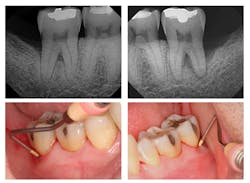

Figure 2: Six-month post-treatment radiographs and photos

Evaluation-A six-month evaluation demonstrated reattachment (see Figure 2). The radiograph of tooth No. 18 exhibited 7.4 mm bone loss on the distal surface, reflecting an increased bone height of 4.4 mm. For tooth No. 31, the radiograph exhibited 6.2 mm bone loss, reflecting an increased bone height of 2.2 mm. Epithelial attachment gain was clinically evident as well (see Table 2). Pocket depths had marked improvement with elimination of furcation involvement on both teeth, decreased mobility of tooth No. 18, and no increase in recession. The patient also submitted three-year post-treatment radiographs taken by the dental hygienist of record (see Figure 3) with evidence of bone stability.